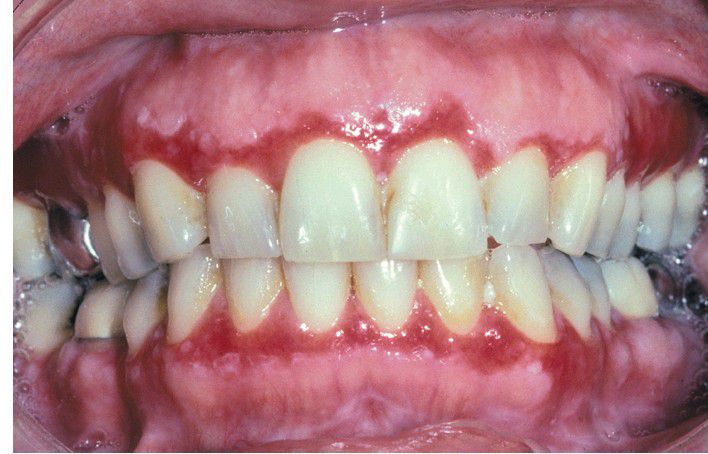

Lichen Planus.

Erosive lichen planus often appears as a desquamative gingivitis, producing gingival erythema and tenderness.